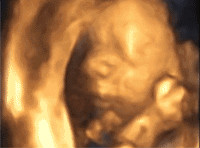

上海百佳|孕早期的NT检查,都检查些什么?

百佳妇产夏日呵护季 | 超声影像检查限时团购